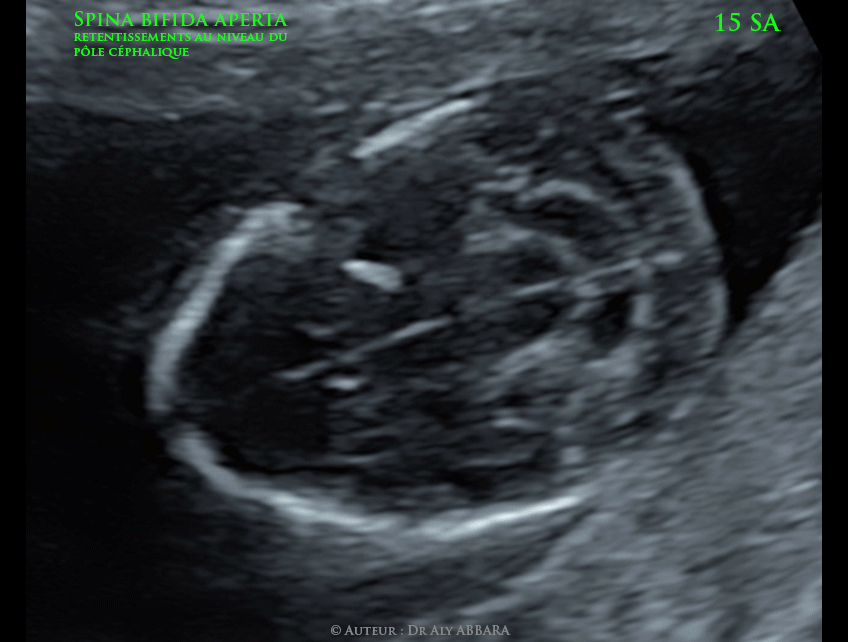

Les retentissements observés chez ce foetus au niveau du pôle céphalique sont :

- Le signe du citron :

Il s'agit d'une anomalie du contours du pôle céphalique fœtal lui donnant, sur la coupe axiale, l'aspect d'un citron par le rétrécissement et l'incurvation du contours céphalique au niveau des os frontaux (feston frontaux) ; cette anomalie peut être expliquée par l'étirement du cerveau fœtal vers la fosse postérieure et vers la base du crâne avec l'adaptation des os frontaux à cette anomalie de la position et du volume du cerveau.

- Le signe de la banane (décrit par Campbell) :

Dans cette anomalie, , l'écrasement et l'étirement en longueur et l'abaissement du cervelet vers la base du crâne et son incurvation vers l'avant lui donnent cette forme particulière qui ressemble à une banane coiffant le tronc cérébral. Le signe de la banane fait partie des élément de l'anomalie d'Arnold-Chiari :

- Il s'agit d'un étirement du tronc cérébral et du cervelet vers la base postérieure du crâne et vers le canal rachidien, rendant parfois le cervelet invisible échographiquement.

- Chez ce foetus, les images échographiques montrent un net rapprochement des cornes postérieures des ventricules latéraux en direction de la ligne médiane sagittale des lobes occipitaux du cerveau.